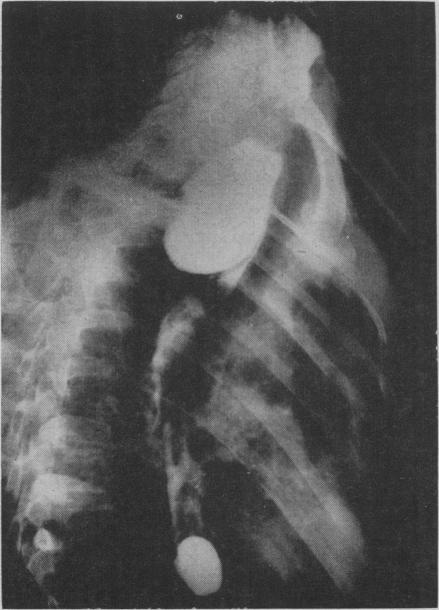

Diverticula of the oesophagus.

Can Med Assoc J. 1957 May 15;76(10):822-31.